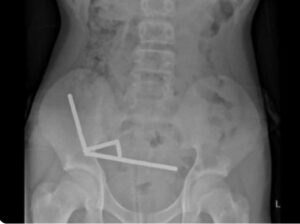

Adolescente passa por cirurgia e perde parte do intestino após engolir cerca de 100 ímãs outubro 28, 2025